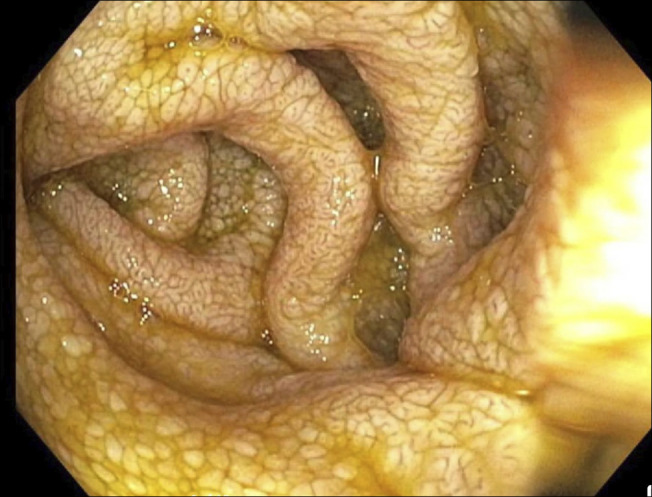

蛋白质丢失性肠病(PLE)通过胃肠道导致蛋白质异常丢失,导致吸收不良和低白蛋白血症。一种罕见的PLE病因是Waldenström巨球蛋白血症(WM),一种以免疫球蛋白M (IgM)单克隆γ病为特征的血液恶性肿瘤。我们报告一个66岁的男性病例,有小肠细菌过度生长和乳糖不耐受史,因胃肠道症状恶化而入院,包括腹部不适、腹胀和水样腹泻。在6个月的时间里,他经历了显著的体重减轻和缺氧。实验室检查显示低蛋白血症、低白蛋白血症和IgM水平升高,伴有大便异常。影像学检查未见明显发现,而内镜检查显示小肠淋巴管扩张样改变。活检结果显示扩张绒毛中有蛋白物质和IgM沉积。骨髓活检证实了WM的诊断。因此,在评估不明原因的PLE时应考虑WM,特别是与胃肠道症状和IgM水平升高相关的PLE。

Protein-losing enteropathy (PLE) results in the abnormal loss of proteins through the gastrointestinal tract, leading to malabsorption and hypoalbuminemia. A rare etiology of PLE is Waldenström macroglobulinemia (WM), a hematological malignancy characterized by immunoglobulin M (IgM) monoclonal gammopathy. We present a case of a 66-year-old man with a history of small bowel bacterial overgrowth and lactose intolerance, admitted for worsening gastrointestinal symptoms, including abdominal discomfort, bloating, and watery diarrhea. He had experienced significant weight loss and anasarca over 6 months. Laboratory tests indicated hypoproteinemia, hypoalbuminemia, and elevated IgM levels, accompanied by abnormal stool studies. Imaging showed no significant findings, while endoscopic evaluation revealed lymphangiectasia-like changes in the small bowel. Biopsy results demonstrated proteinaceous material in dilated villi and IgM deposition. The diagnosis of WM was confirmed by bone marrow biopsy. Thus, WM should be considered when evaluating unexplained PLE, particularly with associated gastrointestinal symptoms and elevated IgM levels.